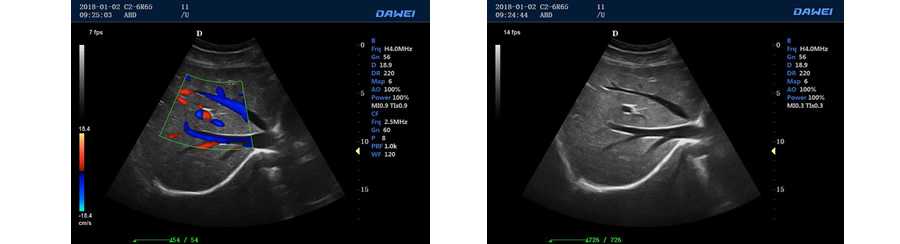

●彩色多普勒血流成像單元

多普勒模式

具有PW脈沖波多普勒和CW連續(xù)波多普勒

取樣容積大小,可視可調(diào)

采樣角度校正:-30-80度

脈沖重復(fù)頻率多段可調(diào)

實(shí)時自動多普勒包絡(luò)描述及自動測量與分析

外周血管 多普勒血流測量與分析